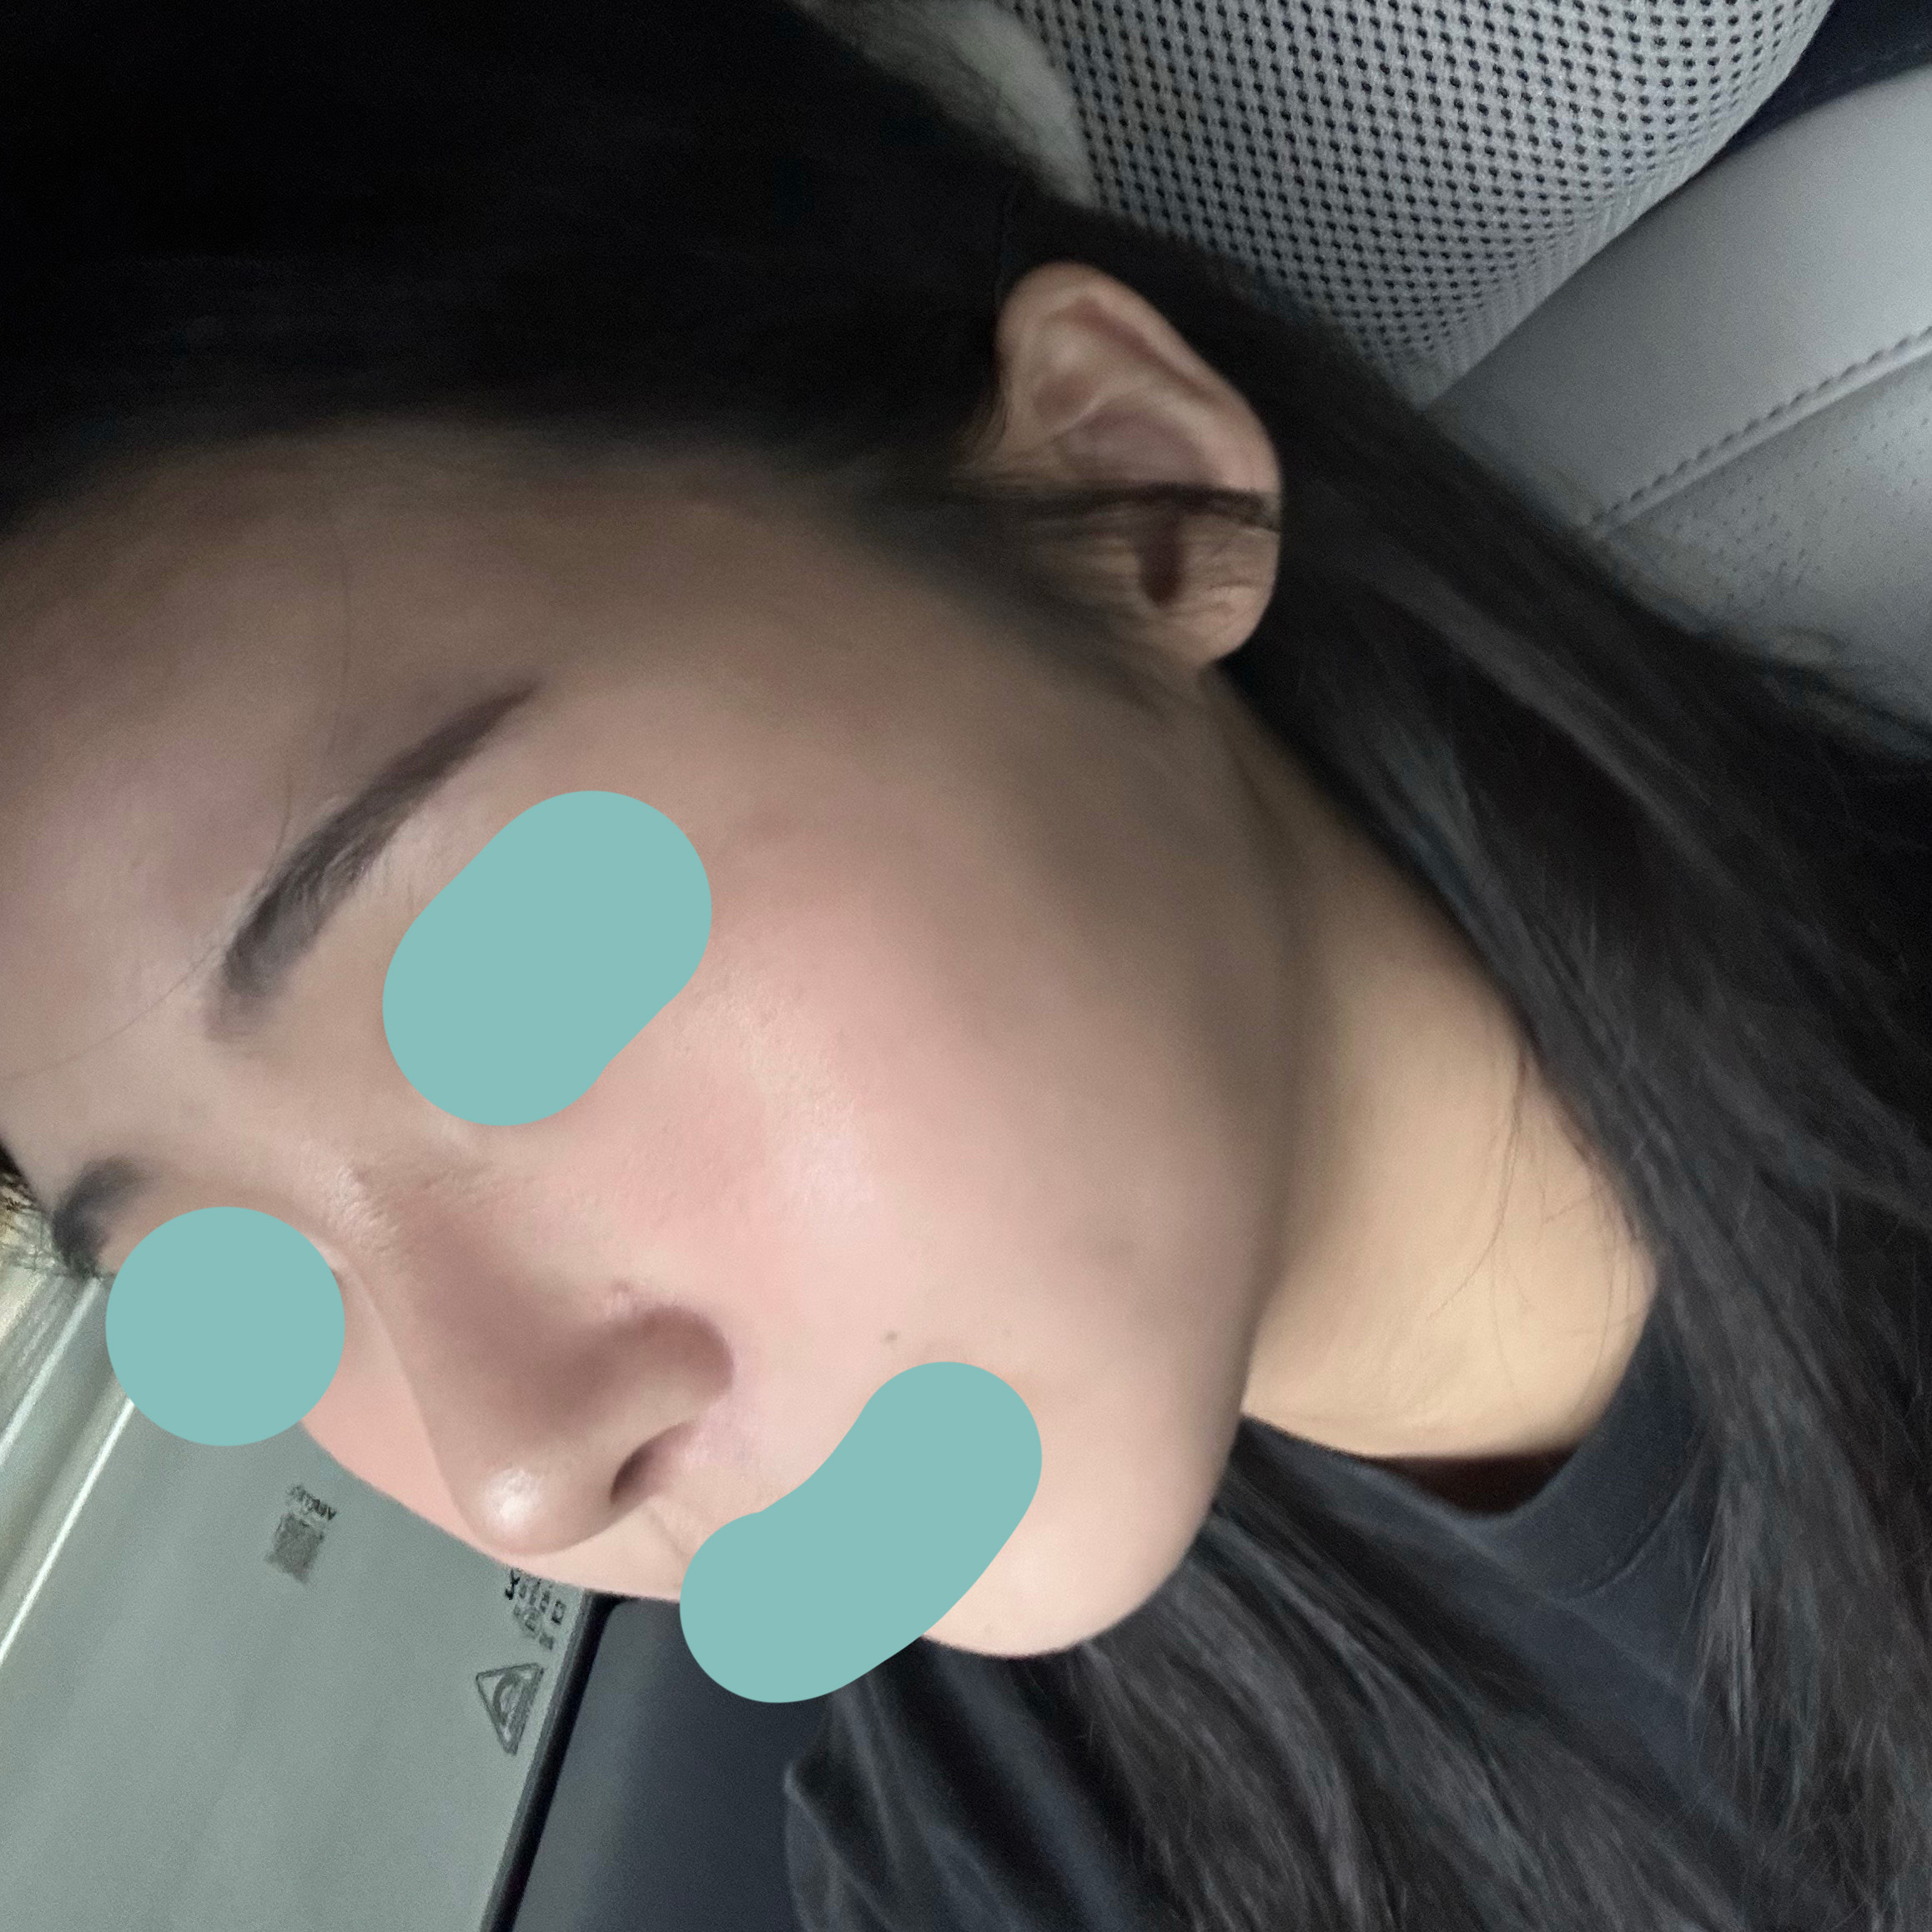

코성형 1개월차 찐 후기:)

1개월차 찐 후기 올려요 :)

지금 제 코는 만족스러우며 아직 한달지만

주마다 코 모양이 달라지는걸 느끼고 있습니다!

보는 사람마다 뭔가 달라졌는데? 뭐야 왜 점점 이뻐져?

이미지가 달라졌어! 이말만 오조오억번 듣는중입니다^_^